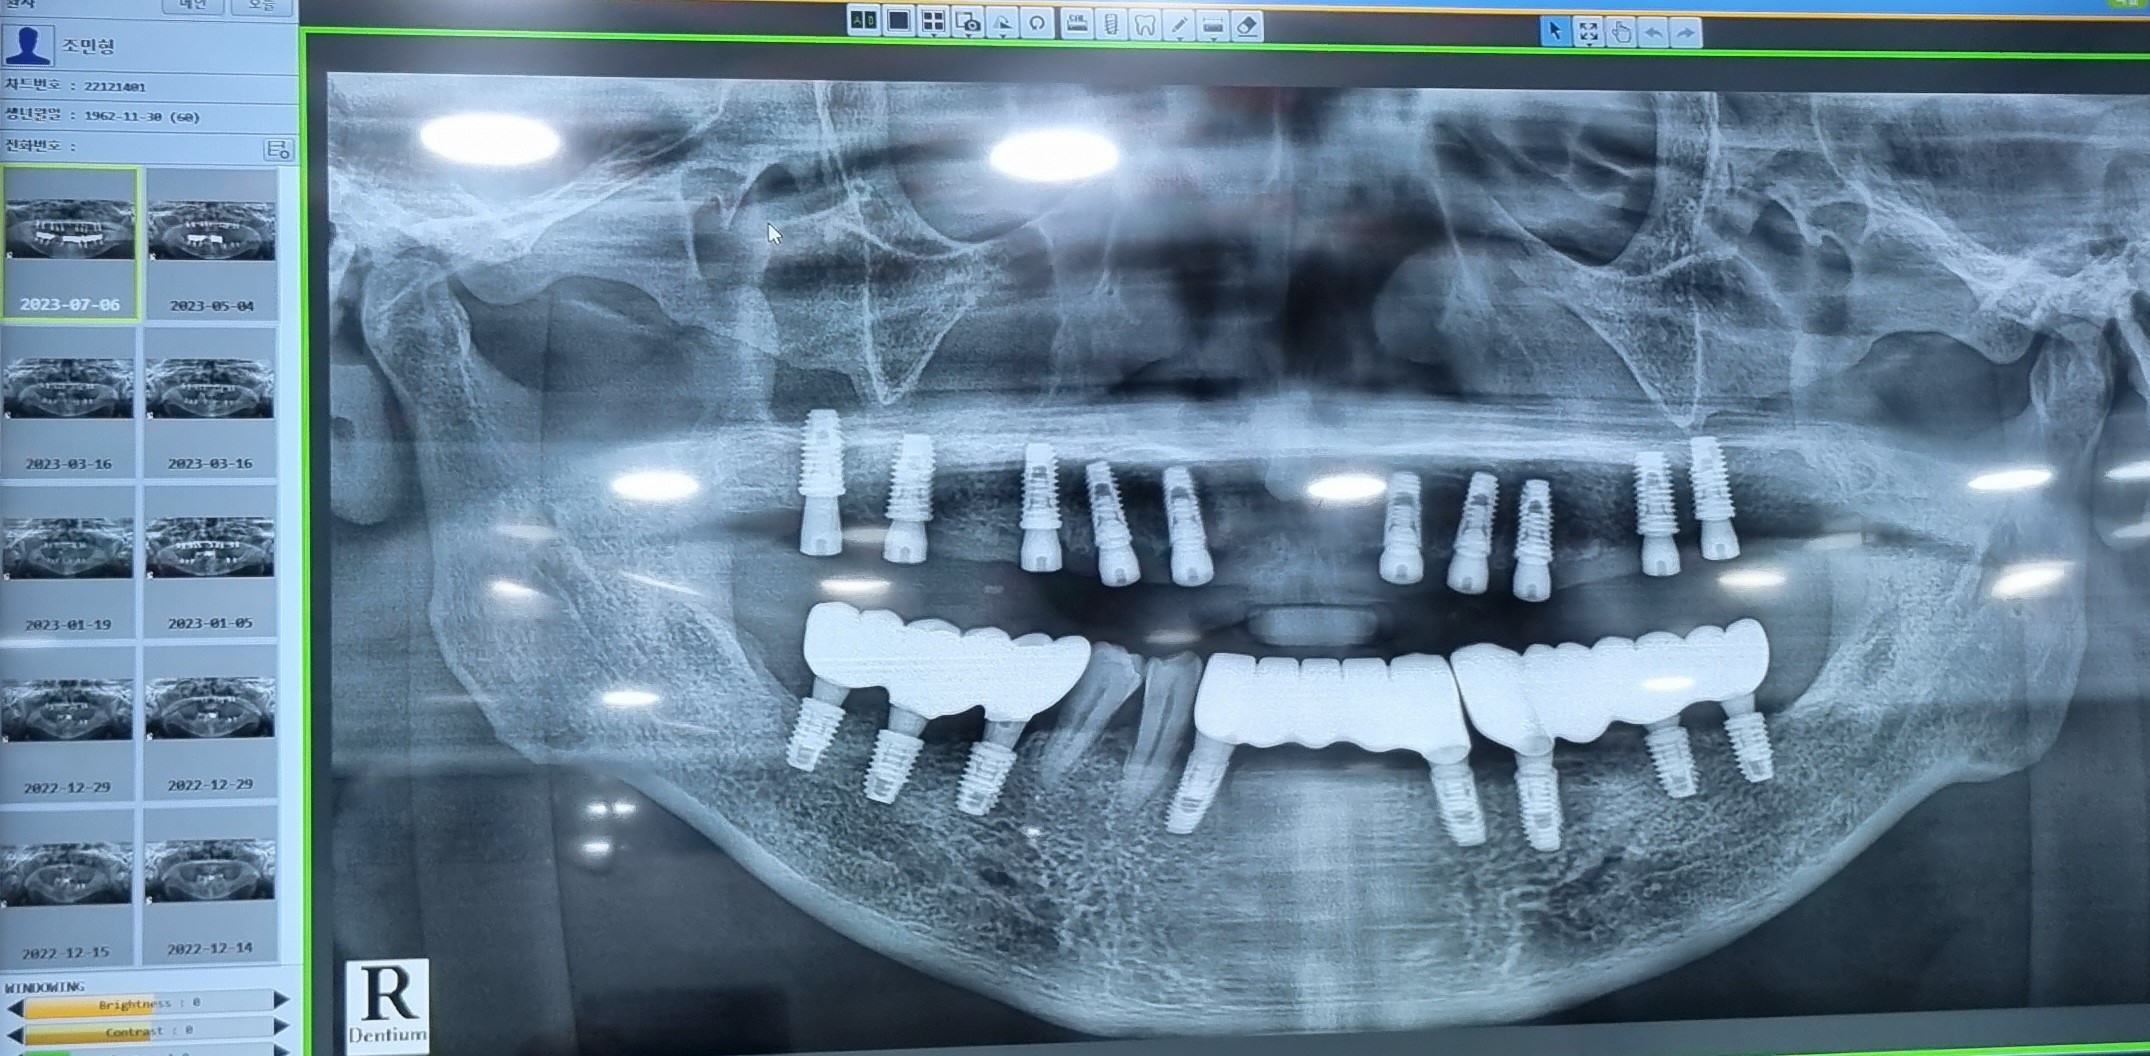

613아랫니 하악下顎 36. 37 41  2차 수술을 진행하였습니다.

6월  20아랫니 하악下顎 36. 37 41 치아齒牙 본뜨기

76하악下顎 36. 37 41 치아齒牙 본뜬후  2주가지나

드디어 하악下顎 보철을  올리는 날이였지요.

완성된  치아齒牙을  실제입안에  끼우고.

오랜  기다림 끝에  ~~~~ ㅉㅉ ~~~ ㅉㅉ

하악下顎 치아齒牙가  모두  완성되었습니다

당일  윗니上顎 10  2차  수술을  진행하였다

713상악上顎 13.12.22.23.24.26.27.14.16.17.치아를 본뜨기

8 3일 오랜  기다림  ~~~~ ㅉㅉ ~~~ ㅉㅉ